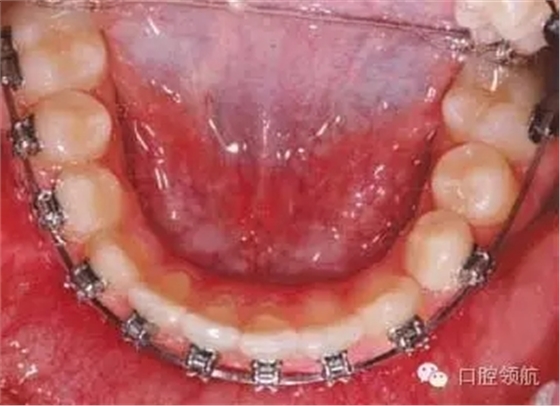

拔除第二恒磨牙后可采用哪種矯治器促進(jìn)下頜第二前磨牙萌出?

可能的選擇包括使用舌弓防止第一磨牙近中移動(dòng),或使用唇擋促進(jìn)第一磨牙遠(yuǎn)中移動(dòng)并豎直。另外,可以在簡(jiǎn)單的下頜固定矯治器上加推簧為第二前磨牙萌出開辟間隙。這種方法可能導(dǎo)致下切牙唇傾前移。這種情況下拔牙6個(gè)月后不要采取主動(dòng)治療措施。豎直并遠(yuǎn)中移動(dòng)第一磨牙期間前磨牙會(huì)自動(dòng)萌出。